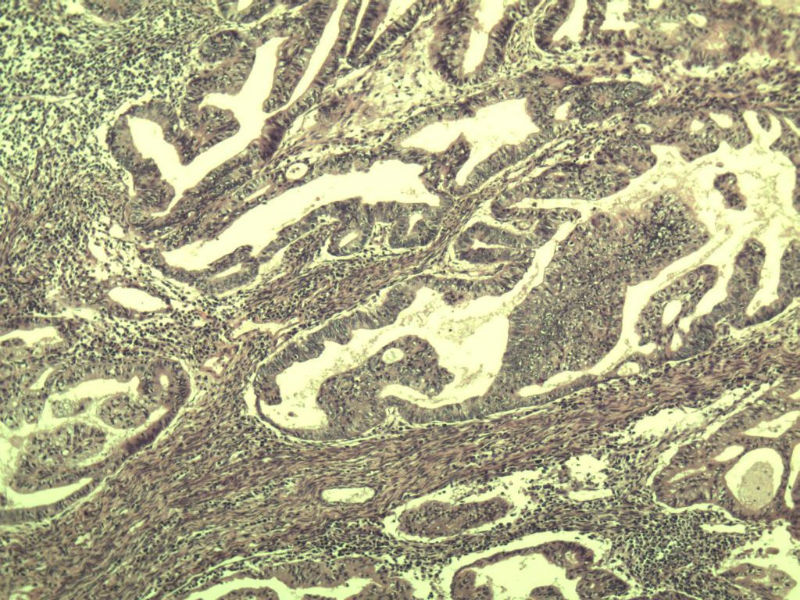

女,57岁,全切子宫一个,宫体体积 9 × 8 × 7 cm3,肌壁厚 2.5 cm,内膜菲薄,部分区域增厚达 0.4 cm(约3*2.5cm区域)。 请问各位老师  这个可以诊断子宫内膜癌了吧?      深肌层没有看到浸润。

患者因"发现下腹部包块1月多"入院  宫体体积 9 × 8 × 7 cm3,肌壁厚 2.5 cm,内膜菲薄,部分区域厚 0.4 cm(约3*2.5cm)。宫颈结构不清,长约 2.5 cm,表面欠光滑。临床诊断宫颈宫腔积液.

宫内膜样腺癌

筛状、迷路样结构

间质消失或者纤维性间质

子宫内膜样腺癌

高分化子宫内膜样癌。浸润浅肌层(深度<1/3肌层)。根据FIGO2009分期,子宫内膜癌局限于内膜层和<1/2肌层,都属于IA期。二者处理不再区别对待。